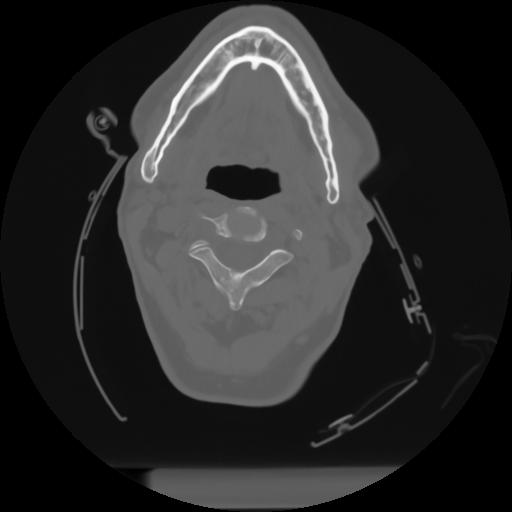

10 P.BLANDAS,,Axial,2.0,P.BLANDAS,,